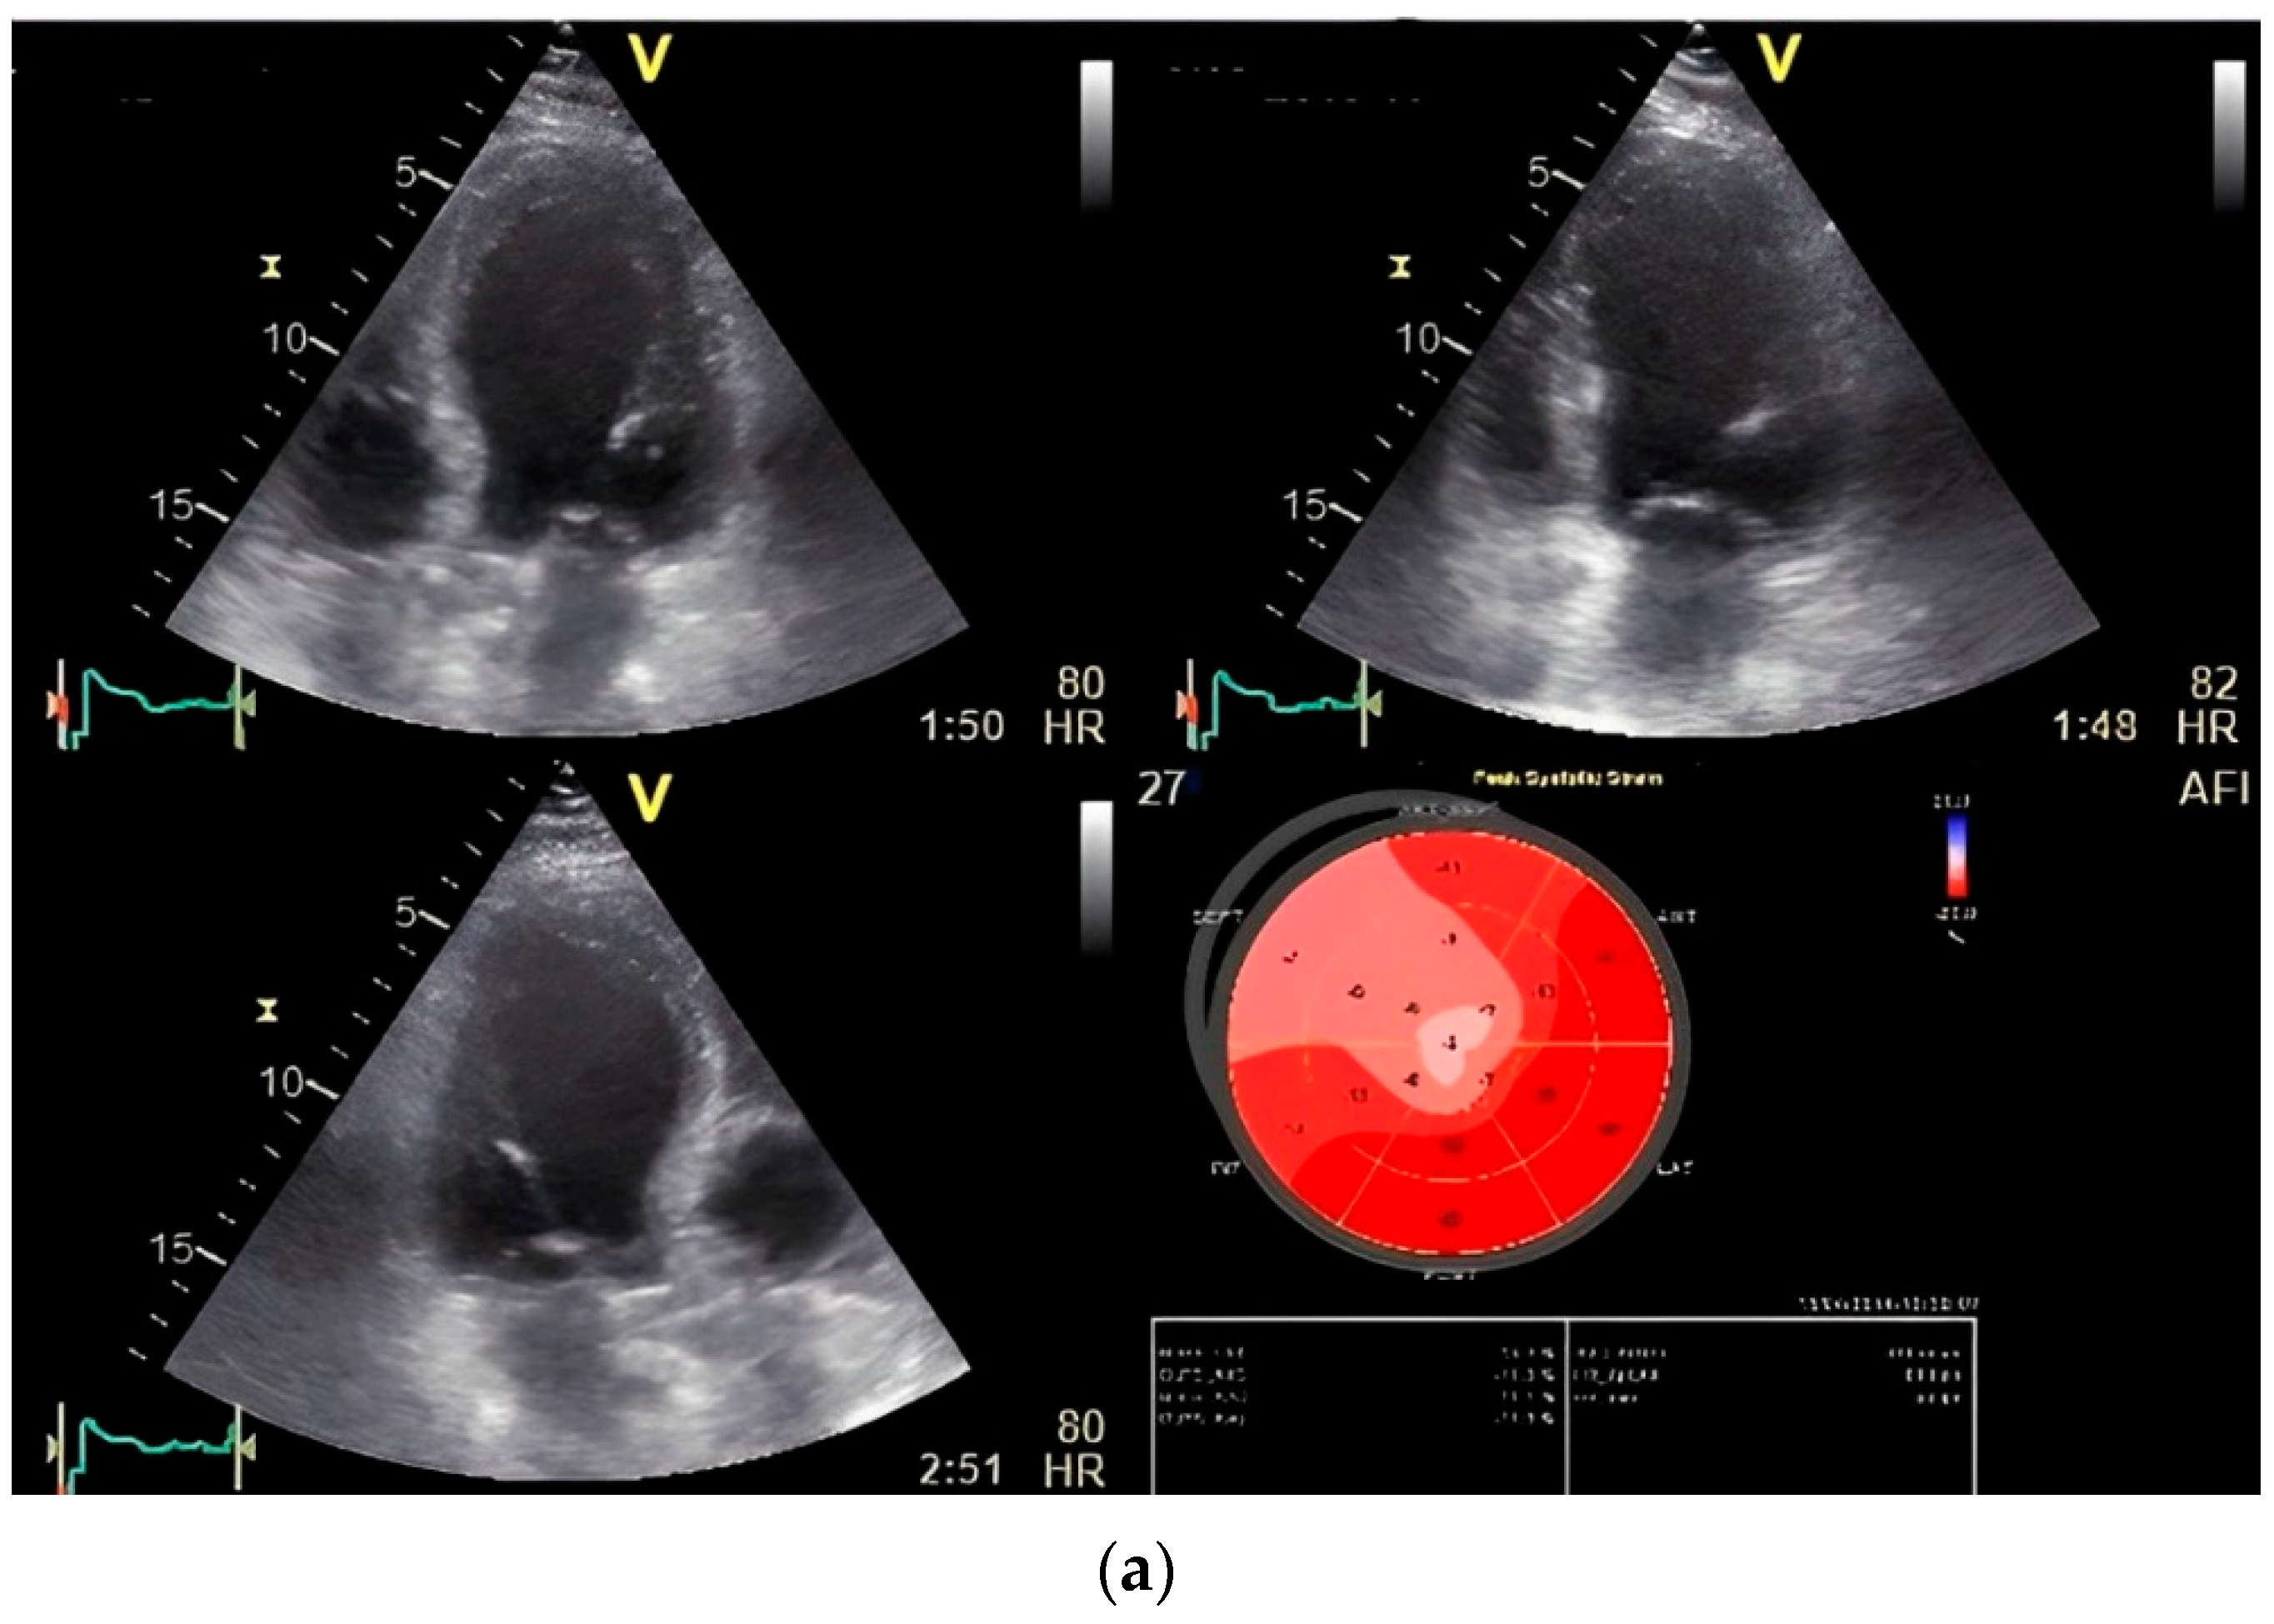

Figure 5.

(a) Global longitudinal strain (GLS) by speckle tracking at rest showing decreased strain in septal region. (b) GLS by speckle tracking under stress (first phase stress at 20 mg/kg/min intravenous infusion of dobutamine) of the same patient showing decreased strain distributed over anterior and anterolateral region (significant left circumflex stenosis was revealed in coronary angiography). (c) Disturbance of T wave dispersion at stress in the same patient.